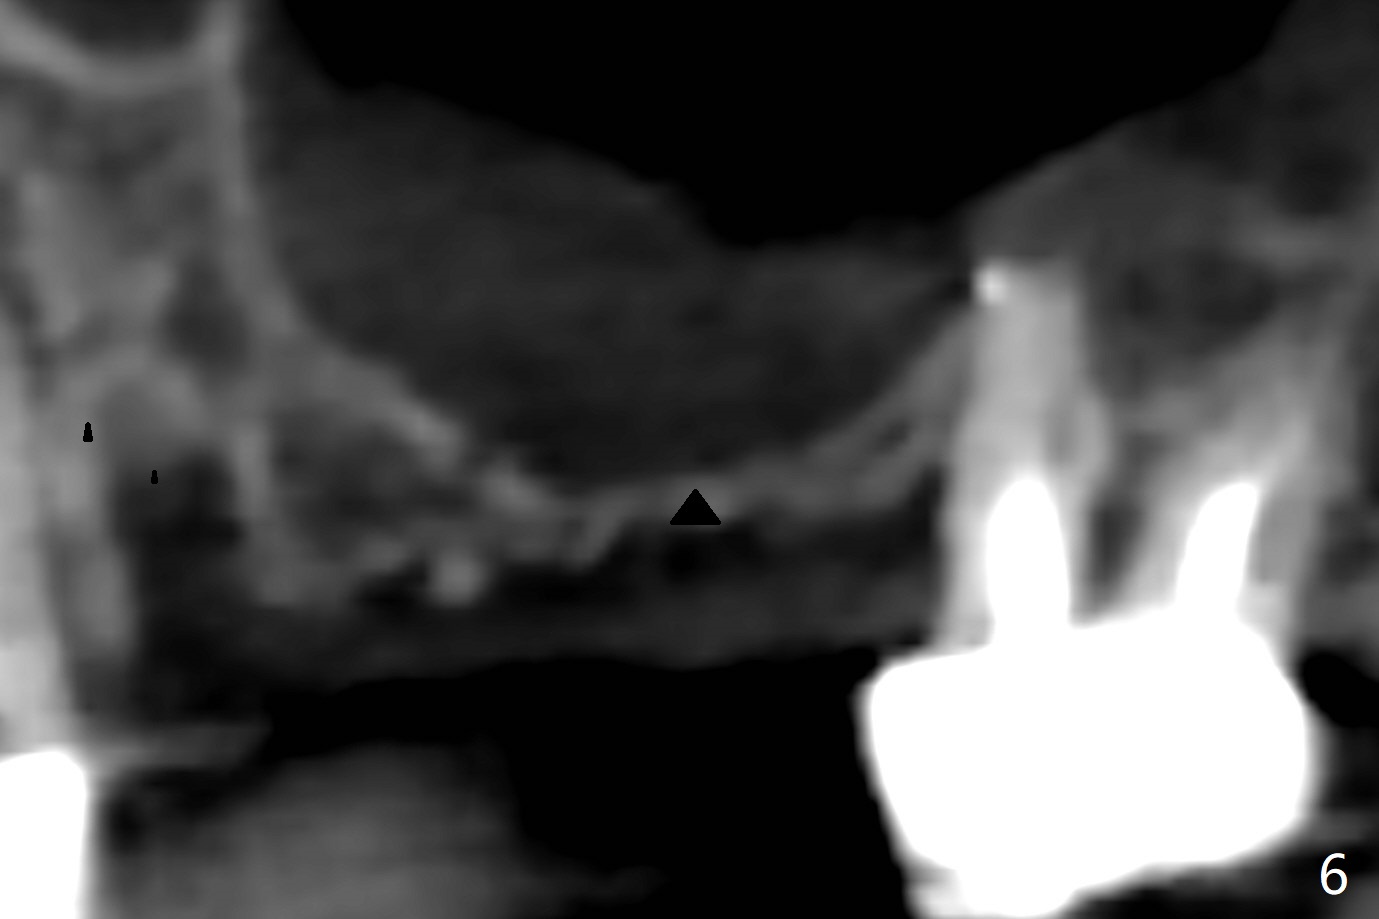

A 68-year-old timid woman is considering implant at #14 twenty months post cementation of #13 and 14 crown (Fig.1). Because of the narrow buccopalatal width (Fig.2 CT coronal section, B: buccal), a 4 mm implant (blue line) seems to be appropriate for the site (Fig.1). After crestal incision and flap reflection, a diamond round bur is used to thin the sinus floor until the bluish membrane is barely visible. An osteotome (Magic Sinus Lifter) is used for penetration. Water lift will be conducted if necessary, considering the already thickened sinus membrane (Fig.3 (CT sagittal section) M). Insert the first PRF membrane, followed by bone graft (not too sticky) repeatedly. Use sensor 1 to confirm lift degree. Try a 4x7 mm dummy FC to test stability. Place a definitive one (probably Magicore) if indicated. Use a second PRF membrane before closure of the wound. After nearly 15 month consideration (including coronovirus), the patient decides to get it done. With incision (Fig.4) and Marking Drill (Fig.5, the sinus membrane barely visible in the middle of the osteotomy (dimple, Fig.6 (black triangle)), the sinus floor does not break upon Magic Sinus Lifter). Later the patient complains of discomfort with tapping. In fact Magic Drill (similar to trephine bur, Fig.7) is used to break into the sinus without membrane perforation (Fig.8). Remember the thick membrane (Fig.2,3). In fact the fractured fragment is attached to the membrane (Fig.9 red lines, green sticky fracture). A small curette is used to further separate the membrane from the bony wall (Fig.10) before insertion of a small piece of PRF and sticky bone. When a 4.5x7 mm dummy implant is incompletely placed with stability (<10 Ncm), the membrane is stretched over the bone graft (Fig.11 M). After removal of the dummy, the major remaining piece of PRF (from 9 cc vial) and more allograft are placed before inserting a definitive implant (same size) with 15 Ncm; still the used to be thick membrane remains intact and stretched (Fig.12 M). The implant is equicrestal buccal, while slightly supracrestal palatal. To prevent implant dislodgement into the sinus and bone graft, a final abutment is placed (Fig.12). The wound is closed with 4-0 PGA, perio glue and perio dressing. The latter dislodges 3 days postop. The wound seems to be healing. No dressing is reapplied.